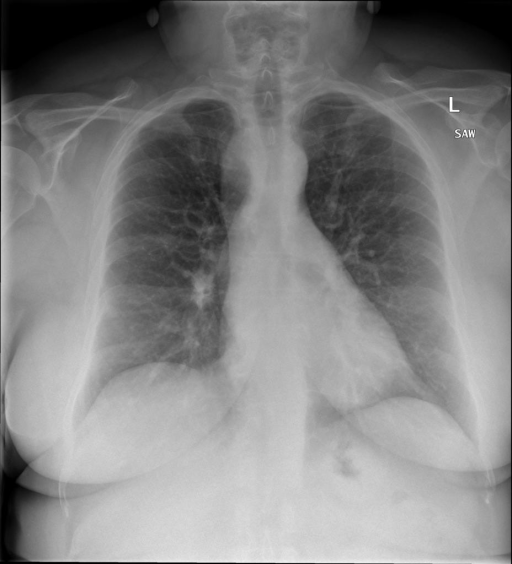

|X光影像|诊疗报告(医生)|

|:-|:-|

||右侧主动脉突出观察到。心脏大小正常。胸部未发现明显的肺气肿、胸膜积液或可疑的肺部病变。报告指出已知右侧主动脉情况正常。|

```bash